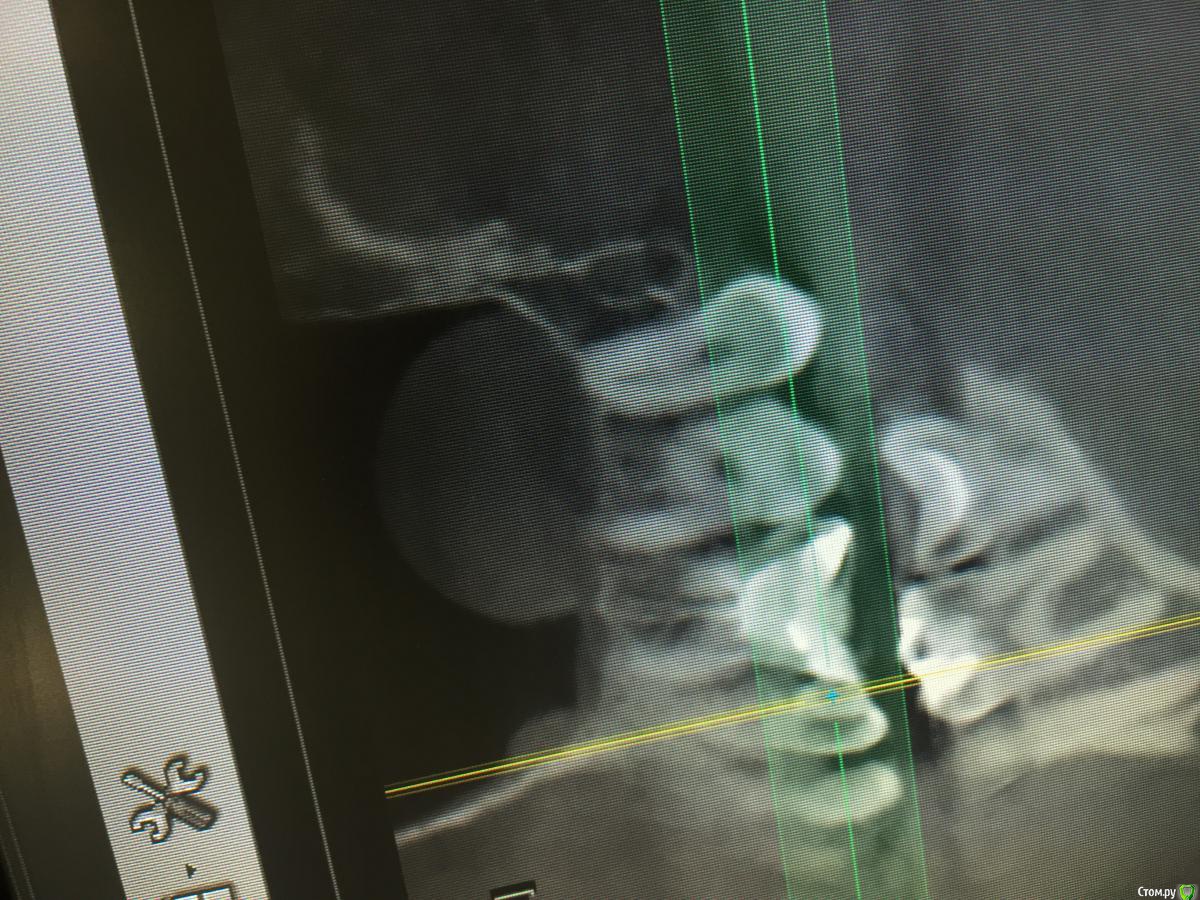

Dr.Yuliya Опубликовано 18 декабря, 2016 Поделиться Опубликовано 18 декабря, 2016 Интересно был ли у Вас в практике похожий случай. Прилагаю снимок . Диагноз хронический апикальный периодонтит. Зуб первичное эндо 17. В процессе механической обработки нёбного канала, удалила плотный тяж пульпы, после была удивлена , что продолжались вычищаться остатки распада. Когда обрабатывала медиальный щёчный канал, заметила что выходит какая то жидкость. Решила сделать носо-ротовую пробу. При выдыхании в нос, при закрытом носе пациента, из канала пошёл экссудат светло- желтого оттенка, так повторила несколько раз. Пациент заметил улучшение дыхания через нос. Последний раз при пробе экссудата не было, поставила гидроокись кальция и отпустила пациента. Как дальше быть? что это могло быть?Предположила , что это экссудат скопившийся под слизистой верхнечелюстной пазухи. Ссылка на комментарий